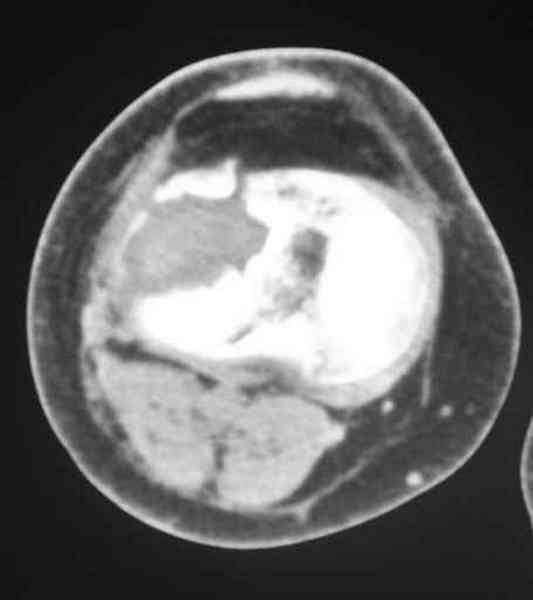

По тактике лечения, более импонирует второй вариант, но наружная плато расколота и туда при нагрузке внедряется н/мышелка бедра, поэтому после дистракции как репонирвать: или стяжными винтами, или изогнутами спицами или субхондральная костная пластика?